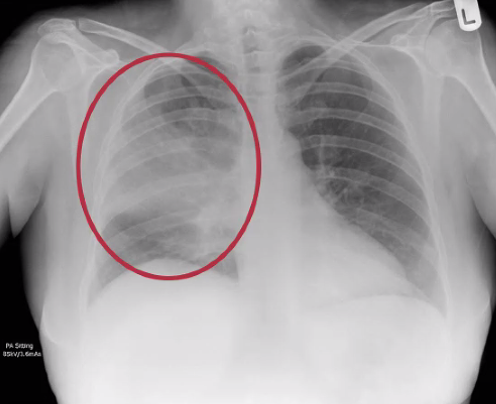

What are the 2 different types of pneumonia on a chest X-ray?

Lobar pneumonia:

Bronchopneumonia:

What type of pneumonia is shown in this image?

this image shows lobar pneumonia